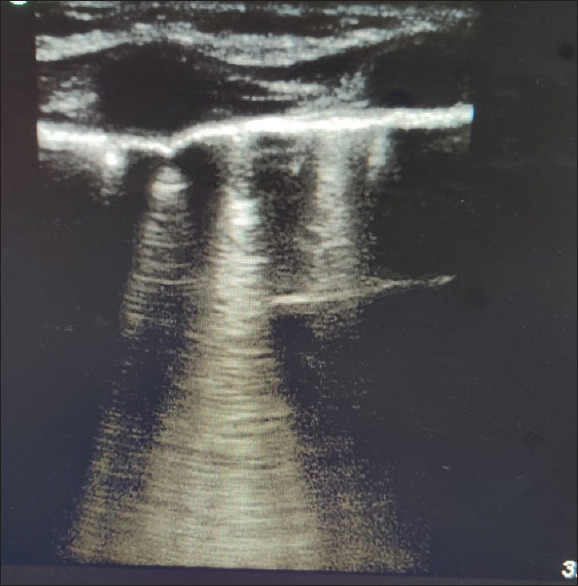

Material and methods: This is a prospective observational study conducted at a tertiary care facility involving children aged 6 months to 12 years who were scheduled for cardiac surgery. A lung ultrasound assessment was carried out before the operation (T0), immediately after the surgery (T1), 6 to 8 hours after surgery (T2), and 18 to 24 hours postoperatively (T3). A score was assigned based on the presence of extravascular lung water indicated by B lines. Pearson's correlation analysis was performed to examine the relationship between the lung ultrasound score of extravascular lung water and the duration of mechanical ventilation and the length of stay in the intensive care unit, with fluid balance, inotrope score, and oxygenation status being analyzed secondarily.

Abstract Image